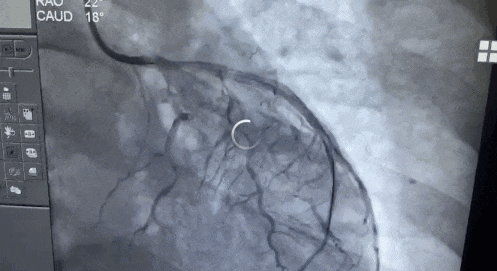

医生立即为他安排行冠脉造影手术

术中发现王先生右冠斑块浸润,前降支中段100%闭塞。医生在前降支置入2枚支架,为王先生成功开通血管。